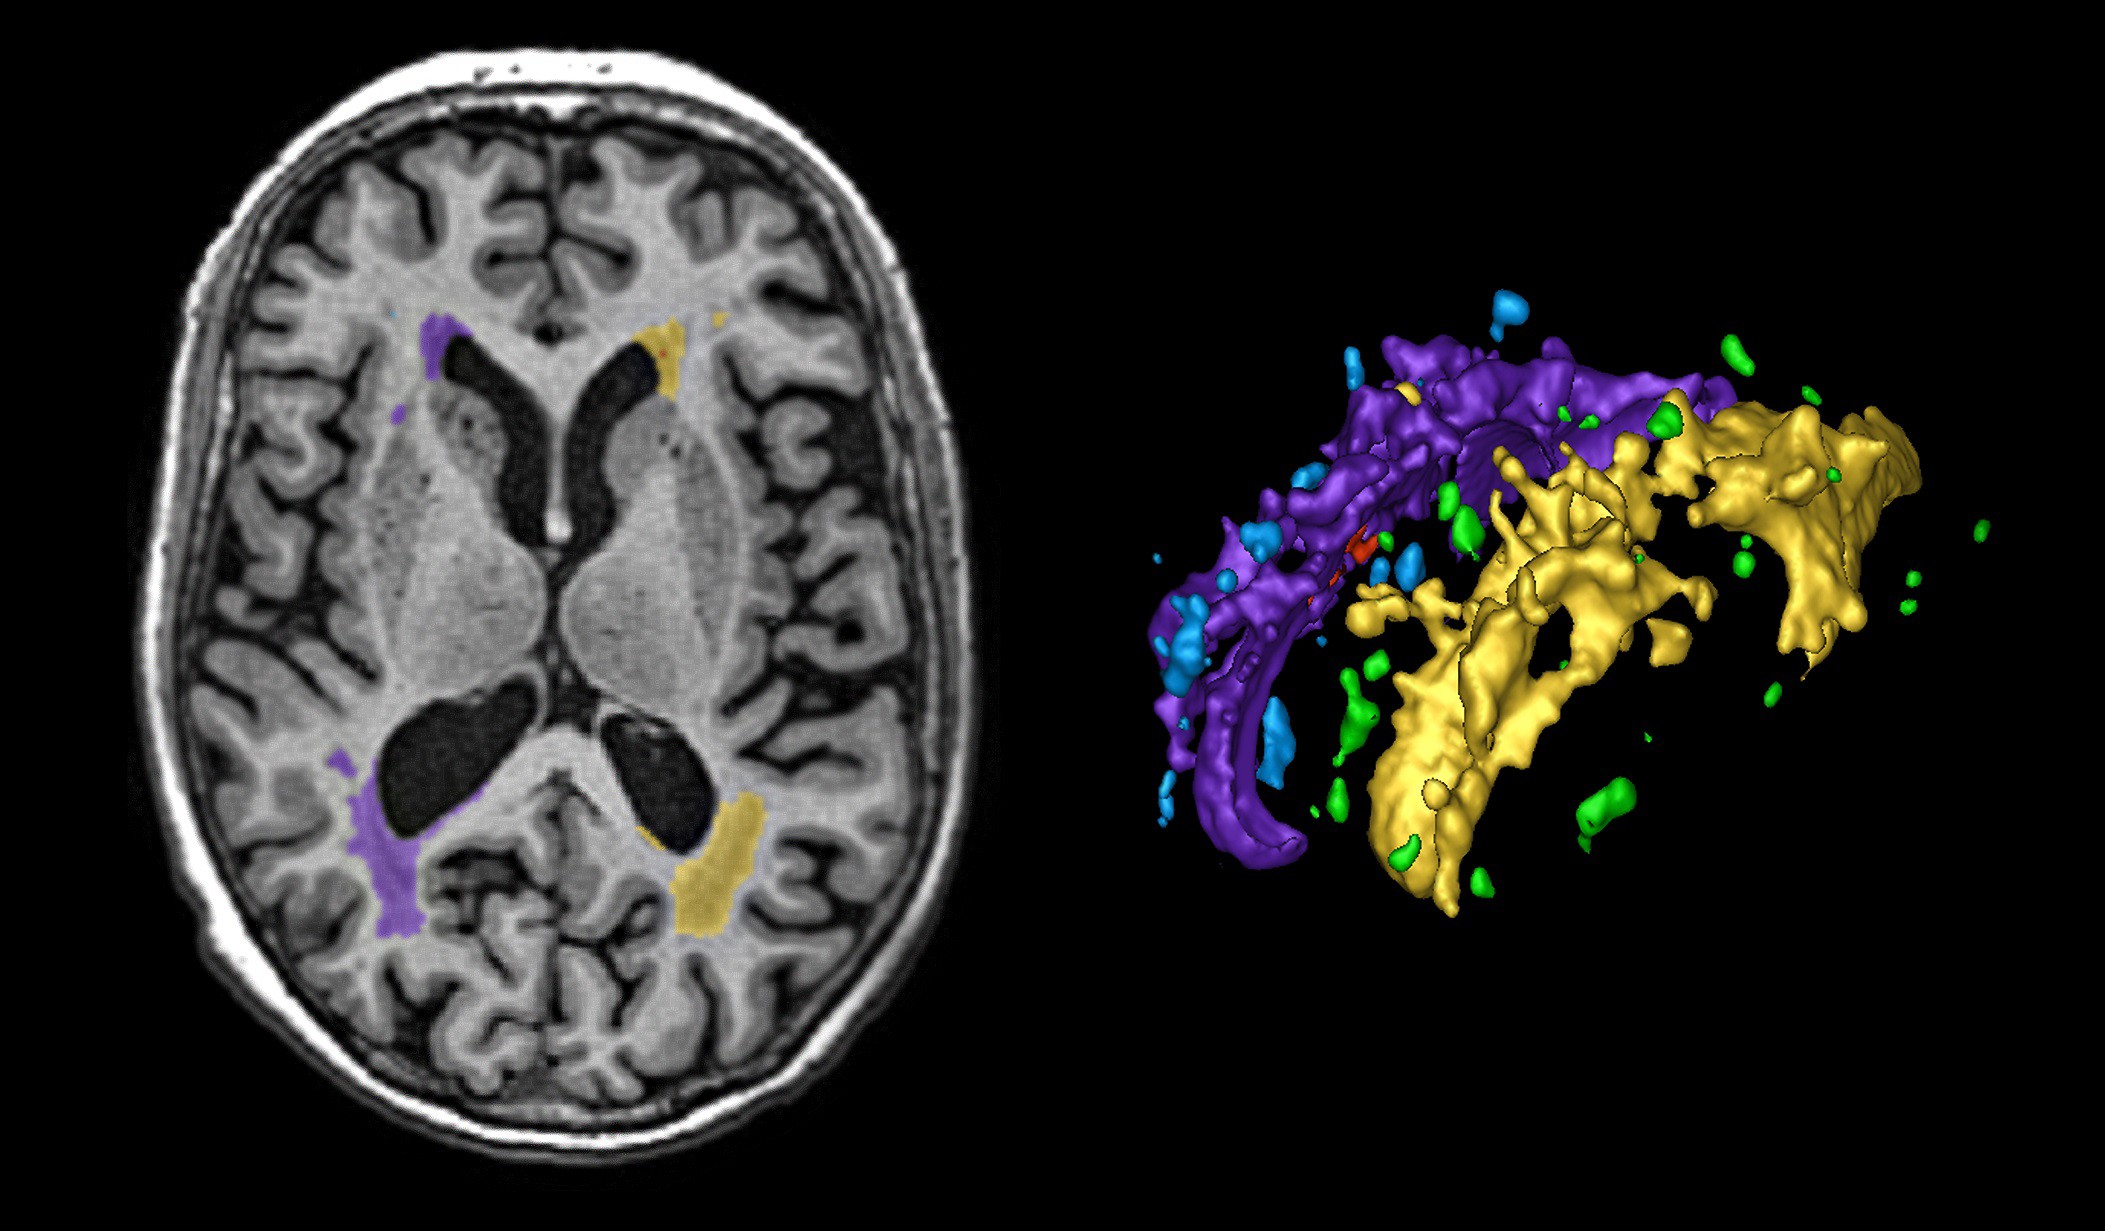

À cette fin, un grand nombre des contributions de la docteure Black découlent de l’étude longitudinale sur la démence de Sunnybrook, un projet de recherche multidisciplinaire qui a commencé au milieu des années 1990 et qui est toujours en cours. Cette étude comporte des évaluations neurocomportementales et d’imagerie standardisées chez des patients « du monde réel » vus à la clinique de la mémoire de Sunnybrook. Après avoir étudié environ 1300 patients qui répondaient aux critères d’admissibilité de base (c’est-à-dire aucune maladie grave et suffisamment en forme pour effectuer les tests) au fil des ans, il est devenu évident que plusieurs personnes étaient atteintes de la maladie des petits vaisseaux qui apparaît en Imagerie par Résonance Magnétique (IRM) cérébrales comme des taches et des plaques blanches, et des points noirs.

L’explorateur de lésions : la quantification 3D de la maladie de la matière blanche

« Environ 95 % des personnes de plus de 65 ans présentent dans une certaine mesure cette maladie des petits vaisseaux, ce qui en fait une maladie très répandue chez les humains vieillissants, et 20 % des personnes de plus de 65 ans présentent des plaques étendues dans la matière blanche, autour des ventricules du cerveau. » Dre Sandra Black

Après près de 200 autopsies de patients, la docteure Black et ses collègues, les docteurs Keith et Gao, ont conclu que ces plaques blanches représentaient un excès de liquide autour des veines profondes du cerveau, dont les parois s’épaississent avec l’âge et l’hypertension artérielle, ce qui rend difficile pour les veines de faire circuler adéquatement le sang et aussi d’éliminer les toxines, comme l’amyloïde, du cerveau.